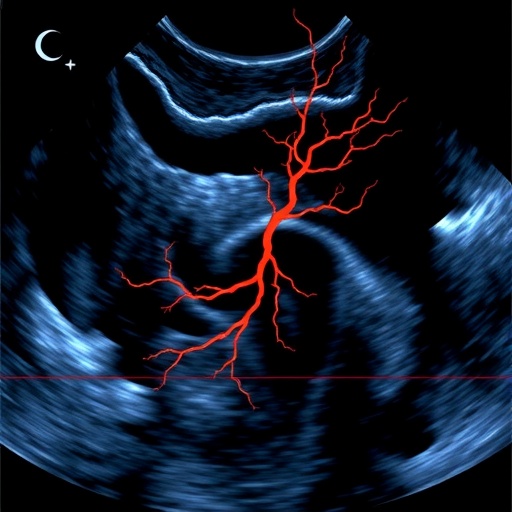

Perhaps most compelling is R-Flow’s application in human liver imaging, where it generated high-sensitivity flow vector maps exhibiting correlations greater than 0.9 with reference standards. This level of precision is critical for evaluating microvascular health in hepatology, particularly in conditions like cirrhosis characterized by complex vascular remodeling and impaired perfusion.

In a rat model of liver cirrhosis, R-Flow revealed striking pathological changes in microcirculation, capturing perfusion transitions from healthy, evenly distributed multipath flows to diseased states dominated by directionally biased hemodynamics. These altered flow patterns correlated closely with the severity of fibrosis and hypoxia markers, suggesting that R-Flow could serve as a powerful noninvasive biomarker to monitor disease progression and therapeutic response.

The technical core of R-Flow involves acquiring beamformed in-phase and quadrature (IQ) data using ultrafast plane-wave ultrasound imaging, which samples the microvascular bed at extremely high frame rates. Subsequent clutter filtering isolates the blood flow signals from stationary tissue echoes, enabling the construction of spatiotemporal image slices along lateral-time (x–t) and axial-time (z–t) planes. By applying the Radon transform to these slices, researchers extract directionally resolved velocity components with exceptional precision. Additionally, axial motion compensation is applied during lateral flow estimation to enhance the continuity of red blood cell trajectories, ensuring smooth and accurate velocity reconstruction.